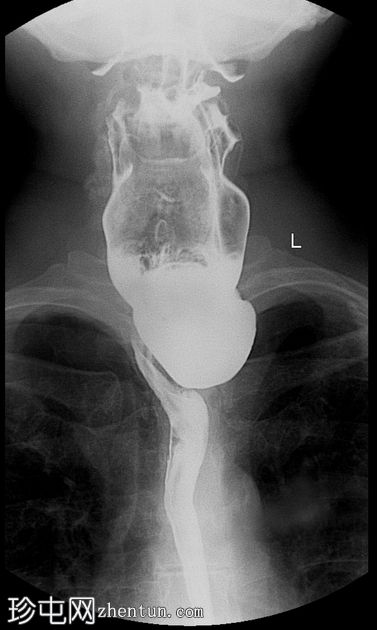

Zenker憩室

间歇性吞咽困难和未消化食物反流

年龄:65岁

性别:男

钡餐检查

可见一充满造影剂的、向后突出的憩室,位于咽食管交界处后壁,大致在T1椎体水平。憩室颈部狭窄,与颈段食管相通。吞咽时憩室充满造影剂,延迟显像显示造影剂滞留。食管其余部分管径和走行正常。未见远端梗阻。

Zenker 憩室是咽后壁的推进性(假性)憩室,起源于 Killian 裂隙。

表现为后正中线向外突出的囊状物,颈部狭窄,位于 T1(C5-C6)水平或略低于该水平。

钡餐侧位片显示最佳。